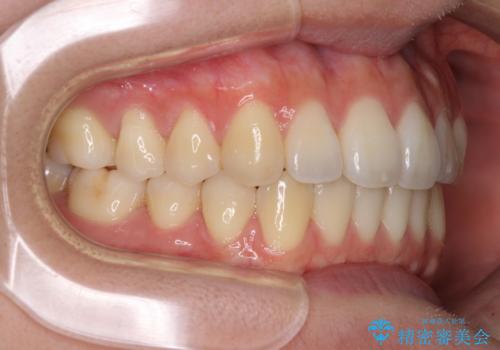

オープンバイトでかみにくい インビザラインによる矯正治療

- 前歯の上下スペースによる食べにくさを気にして来院された患者様です。

インビザラインにより上下の前歯の隙間を閉じていくこととしました。

上下の奥歯を圧下させるようにすることで、前歯を接触させるように計画しました。

上下の隙間に舌が入り込むことがオープンバイトの原因であったため、舌の筋肉のトレーニングも並行して行い、後戻りの抑制を図りました。